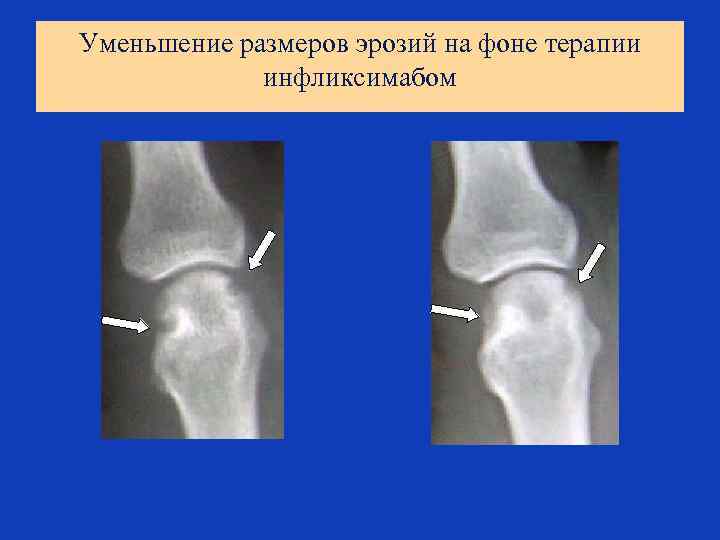

АНТИЦИТОКИНОВАЯ ТЕРАПИЯ РЕВМАТОИДНОГО АРТРИТА Основные провоспалительные цитокины, участвующие в патогенезе РА Антицитокиновые препараты для терапии ФНО МАТ – инфликсимаб (гуманизированные) - адалимумаб (человеческие) Химерный рецептор - этанерсепт ИЛ-1 Рецепторный антагонист ИЛ-1 МАТ ИЛ-6 МАТ против рецептора ИЛ-6 (тоцилизумаб) ИЛ-17 МАТ в разработке

Уменьшение размеров эрозий на фоне терапии инфликсимабом